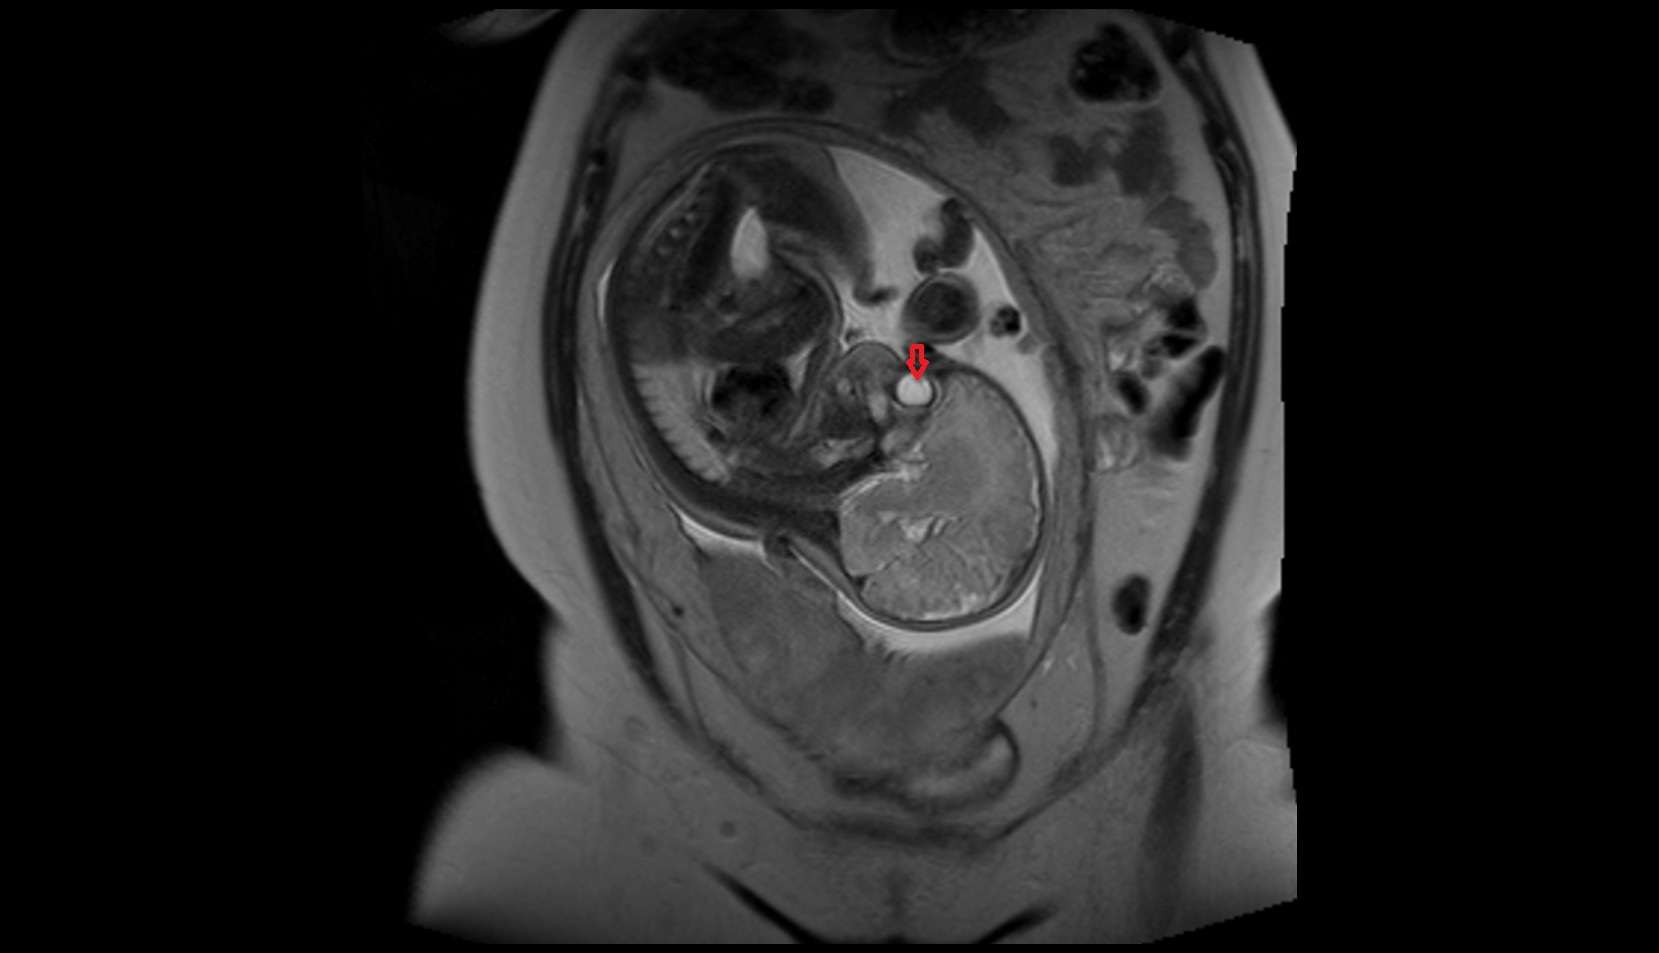

- Placenta

- Uterus (pregnancy)

- Amniotic fluid

- Umbilical cord

- Fetal brain

- Fetal pons

- Fetal cerebellum

- Fetal fourth ventricle

- Fetal spinal cord

- Fetal Heart

- Fetal aorta